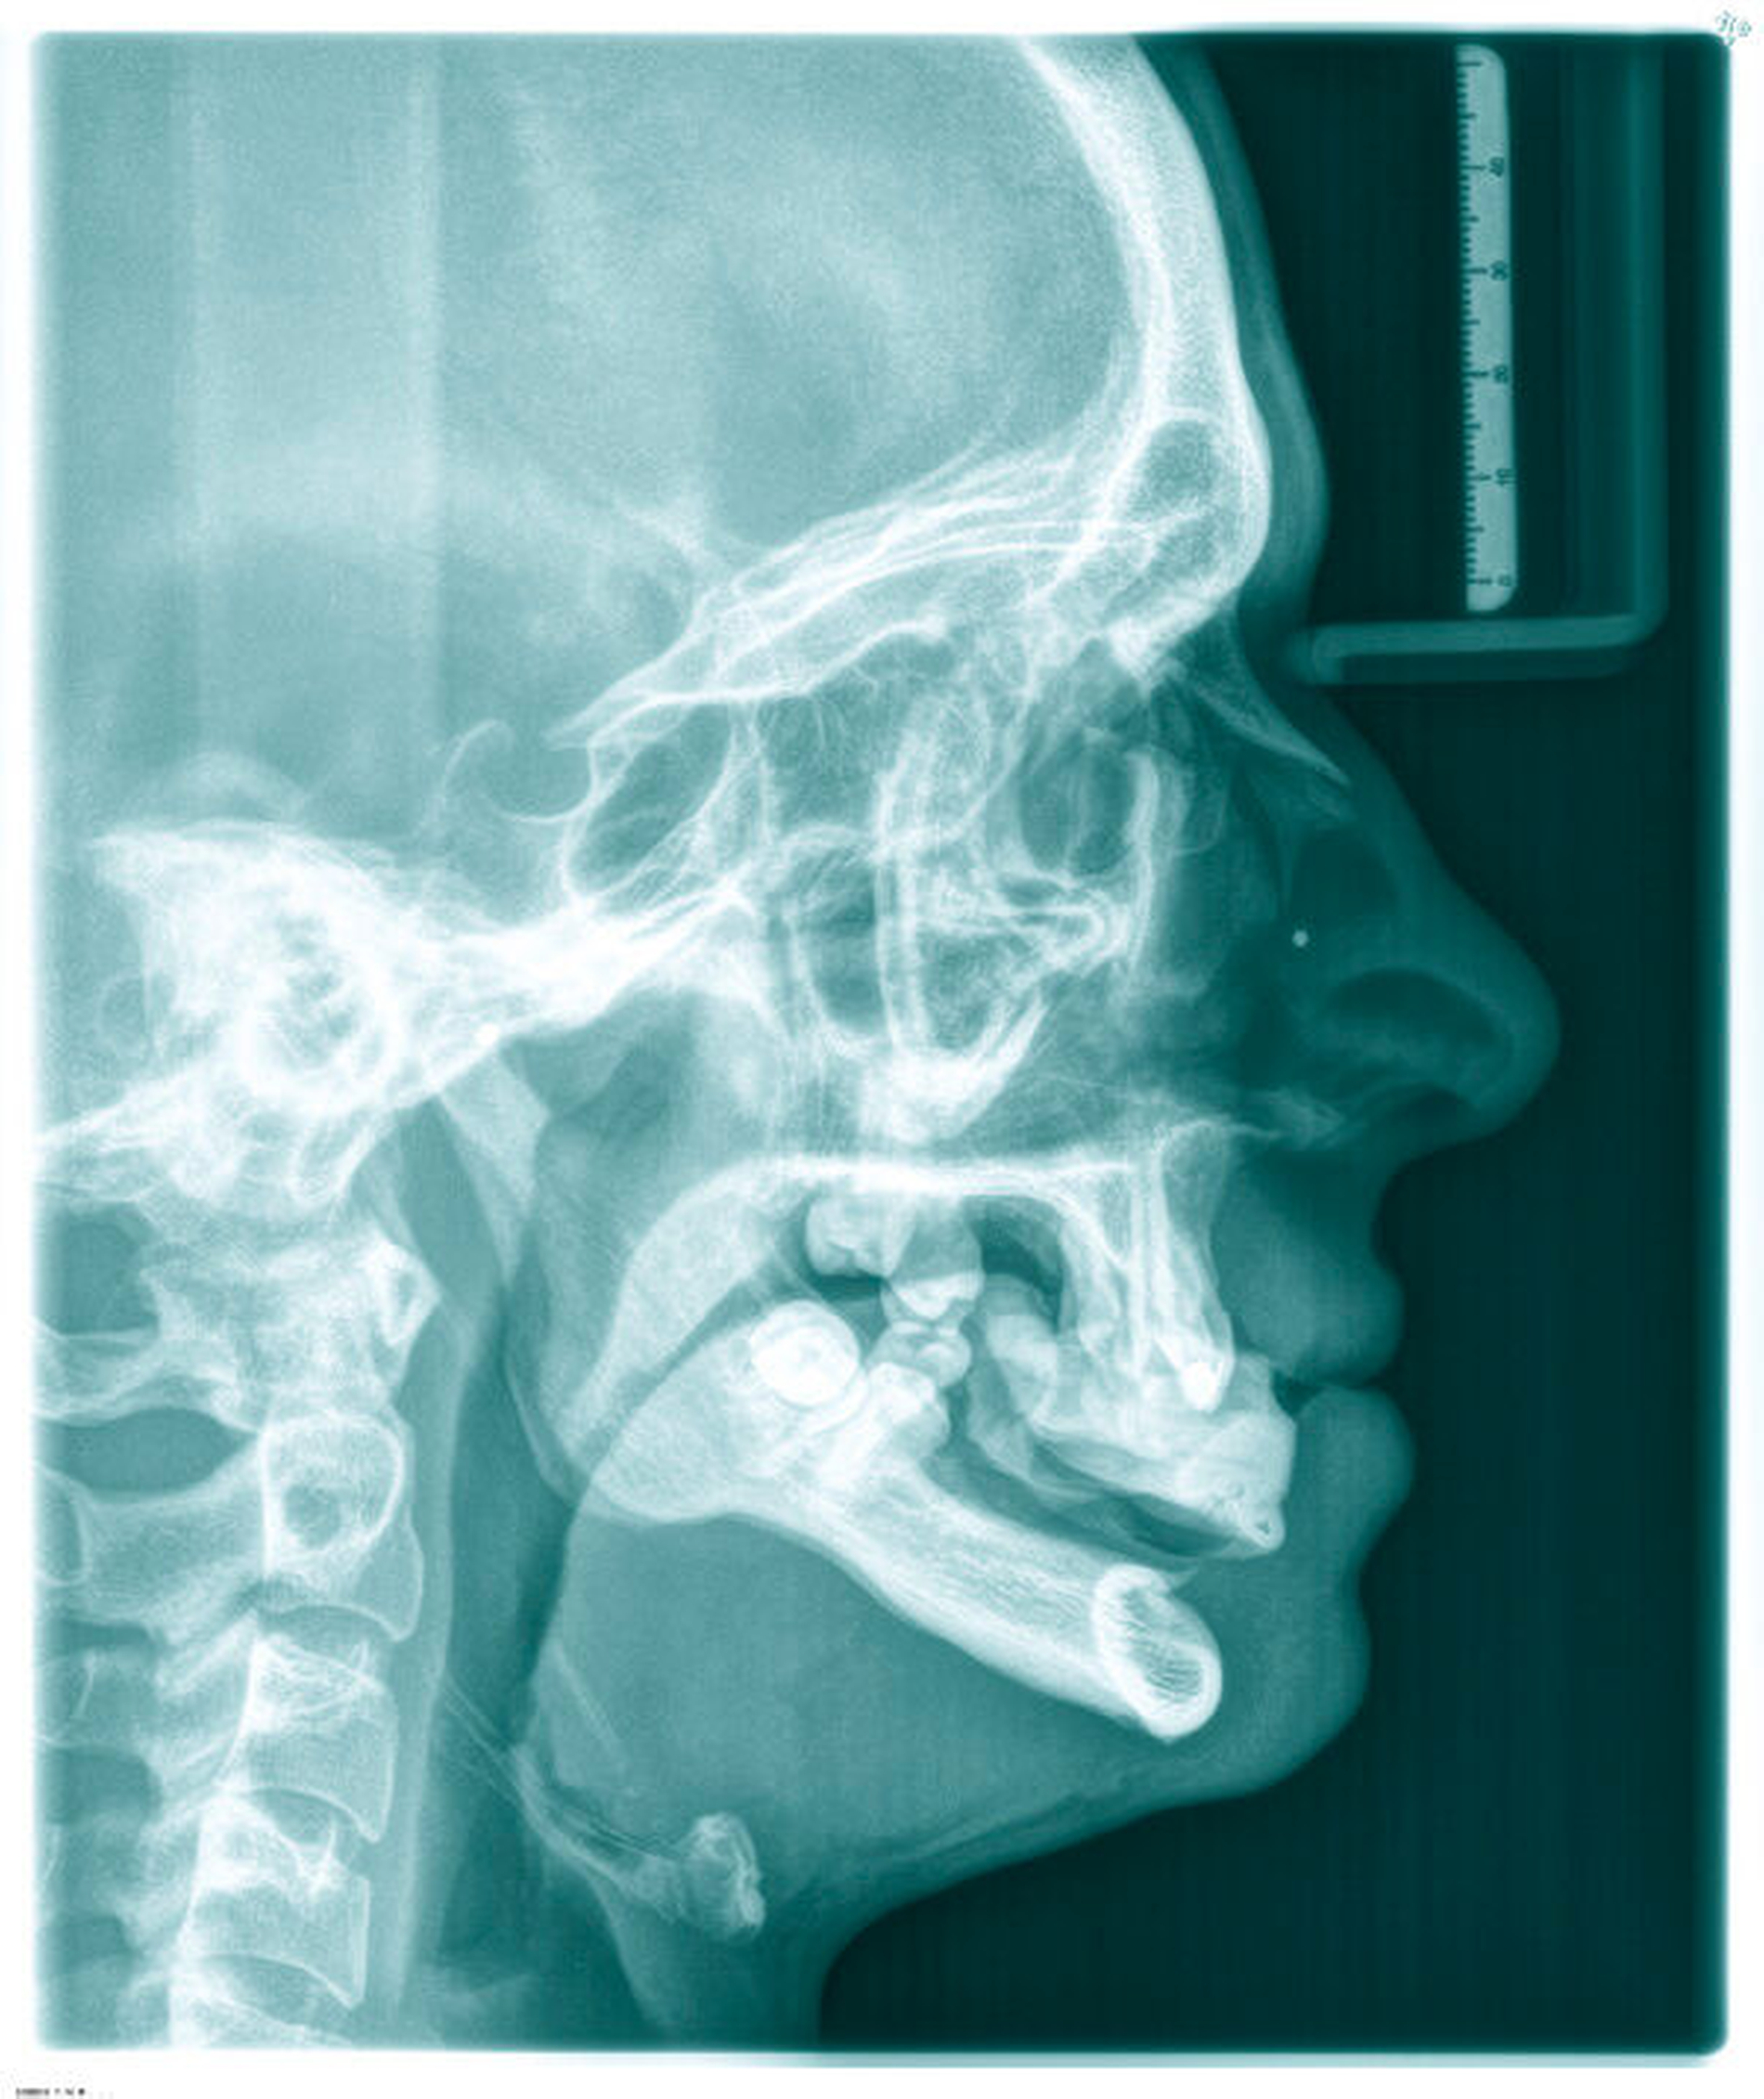

Anschließend wurde eine bimaxilläre Umstellungsoperation (in der Le-Fort-I-Ebene und nach Obwegeser/Dal Pont) durchgeführt (Abbildung 5). Hierfür wurde für den OP-Splint eine provisorische Implantat-getragene Prothese im Unterkiefer angefertigt, so dass die Implantate letztlich auch zur Eingliederung des OP-Splints dienten (Abbildungen 6 und 7). Zusätzlich konnte postoperativ durch die Implantat-getragene Prothese die Okklusion gesichert und das Risiko eines Rezidivs im Sinne einer Okklusionsverschiebung minimiert werden [Ohba et al., 2015].